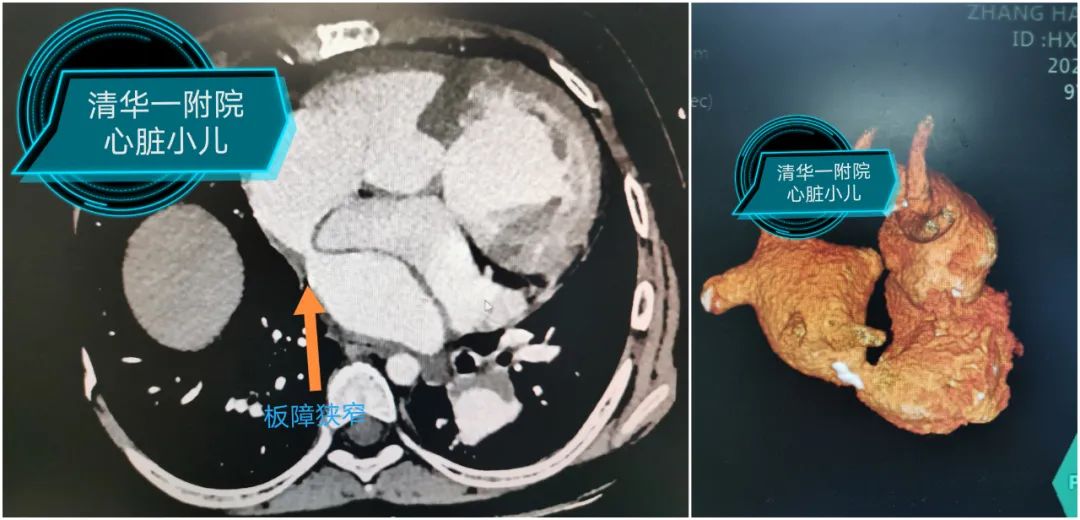

术前CT提示:肺静脉板障梗阻最窄处仅5mm;超声提示:板障入口处血流速度加快,最大前向血流速度为1.8m/s。

2020年,新的肺动脉支架进入临床,陈国良也相继成功实施了几例肺动脉狭窄支架植入术。肺动脉支架小巧的外径、强大的支撑力及优秀的柔顺性给他留下了深刻的印象,同时也给他带来灵感:如果在肺静脉板障狭窄部位植入支架,那么肺静脉淤血便可迎刃而解。确定了治疗方案,下一步就需要确定手术方式了。介入治疗虽然创伤小、恢复快,但双调转术后没有理想的手术入路,唯一的途径是通过股动脉入路,经心室过二尖瓣进入心房,再通过狭窄的板障。此种方式路径长且曲折,导管很难到位,心导管造影过程也证实了术前的推断。靳永强结合患儿的CT及心导管造影认为,可试行右侧肋间切口暴露心房,然后经心房切口将支架和球囊系统通过狭窄部位,此方法不但路径短,而且靠近狭窄部位,是实施支架植入最理想的手术入路。但患儿为复杂心外科术后,肺组织粘连严重,而且合并严重的肺高压,术中一旦损伤肺组织可能出现严重的出血,甚至危及生命。经过充分的术前评估和充分准备后,手术如期而至。

手术选择在杂交手术室进行,在几乎没有明显出血的情况下,靳永强顺利游离肺组织,显露左侧心房。在食道超声的引导下准确选择心房穿刺部位,使穿刺部位在板障狭窄的正下方,顺利将球囊支架系统通过狭窄部位;采用食道超声及X线下确定支架植入部位,操作如行云流水般一次性扩张成功,食道超声及导管测量板障处血流畅通,无明显压差。患儿术后恢复顺利,3小时后撤除呼吸机,第二天便转回普通病房。回到病房的小千活动量明显好转,睡觉时终于可以平卧了。术后超声提示肺动脉压力明显降低,左心室的射血分数也恢复至正常,甚至主动脉瓣的反流也从中量降至少量。